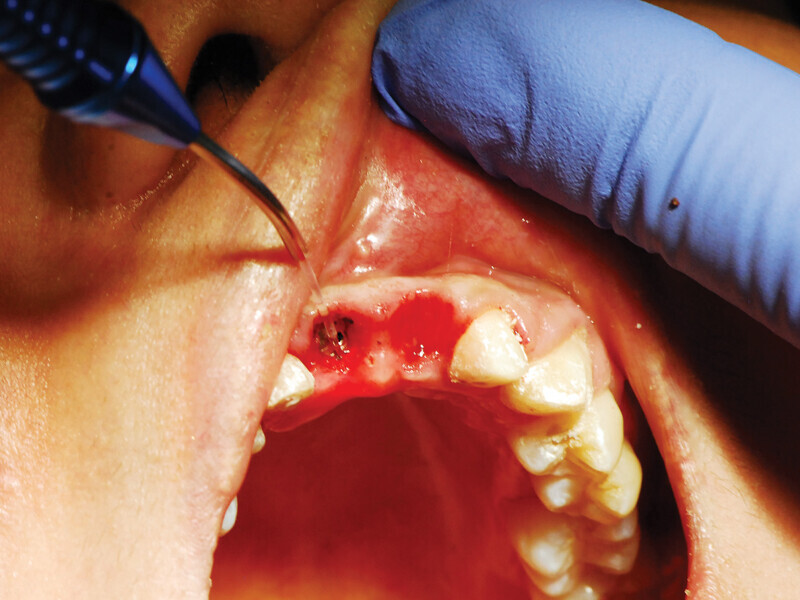

Fig. 5: When minimal keratinized gingiva is present, the diode laser is utilized to make an incision distal-mesially, and the tissue is spread conserving all of the attached gingiva present. (Photo provided by Dr. Gregori M. Kurtzman)